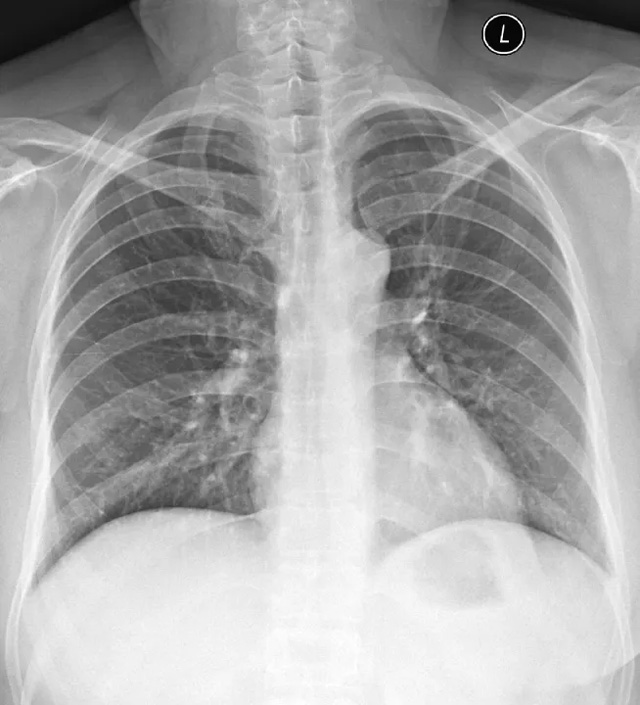

X線定位真空輔助旋切術是對臨床觸診和B超檢查均為陰性而X線片顯示的微小病變在X線立體定位引導下,將真空旋切刀置入乳腺可疑病灶區進行旋切及組織病理學檢查的一種乳腺微創新技術。